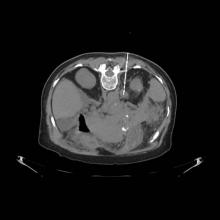

Syed F. Zaidi, M.D., president of Radiology Associates of Canton (RAC) and chief executive officer of RadHelp LLC announced his group, along with hospitalists at Aultman Hospital in Canton, Ohio have reduced patient length of stay (LOS) by three days for inpatients recommended for computed tomography (CT) biopsy.